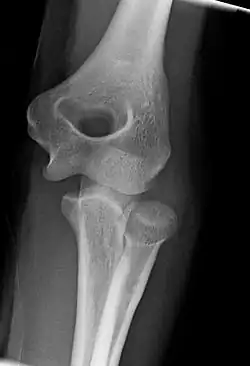

Left: Lateral X ray of a dislocated right elbow

Right: AP X ray of a dislocated right elbow

The types of disease most commonly seen at the elbow are due to injury.

X-ray of ventral dislocation of the radial head. There is calcification of annular ligament, which can be seen as early as 2 weeks after injury.[29]

Elbow dislocations constitute 10% to 25% of all injuries to the elbow. The elbow is one of the most commonly dislocated joints in the body, with an average annual incidence of acute dislocation of 6 per 100,000 persons.[30] Among injuries to the upper extremity, dislocation of the elbow is second only to a dislocated shoulder. A full dislocation of the elbow will require expert medical attention to re-align, and recovery can take approximately 6 weeks.